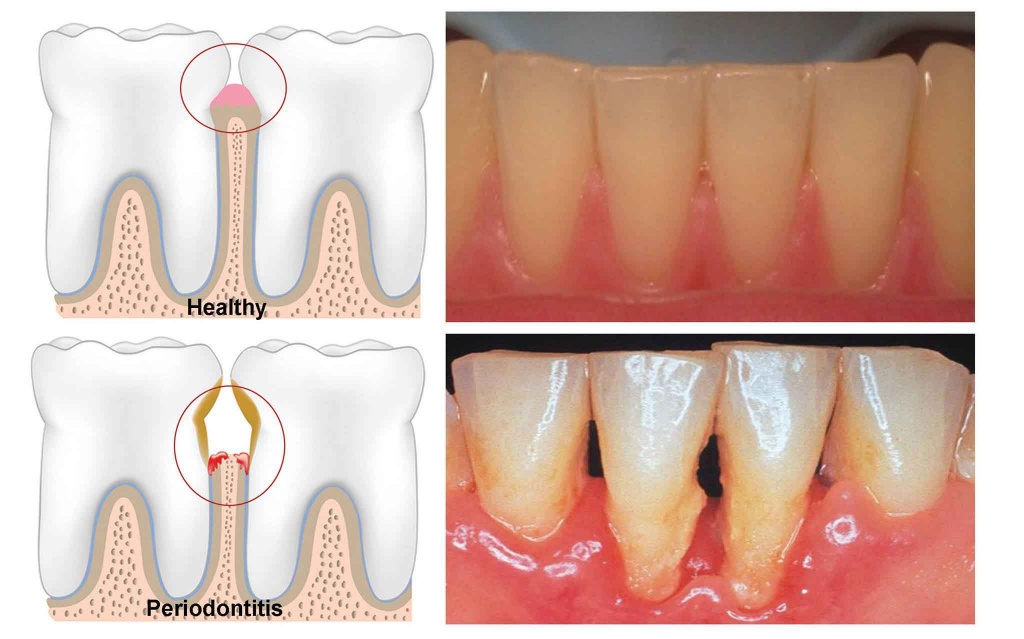

풍치(치주염)란 쉽게 말해서 치아의 뿌리를 잡아주는 치조골이라는 뼈가 주저앉아 치아가 시리고 흔들리는 상태를 말합니다.

치아 주위 조직의 염증은 진행 정도에 따라 치은염과 치주염으로 나누는 데 잇몸에만 국한된 형태가 치은염, 염증이 잇몸을 넘어 치주인대와 치조골까지 진행된 경우를 치주염이라고 합니다.

치은염의 경우는 일반적인 염증의 증상과 같이 잇몸이 빨갛게 되고 출혈이 있을 수 있는데, 초기에는 칫솔질만 꼼꼼히 해도 어느 정도 회복이 가능하나, 염증이 진행되어 치주염으로까지 진행된 경우에는 계속해서 구취가 나며, 치아와 잇몸 사이에서 고름이 나오고, 저작 시에 불편감이 생기게 됩니다.